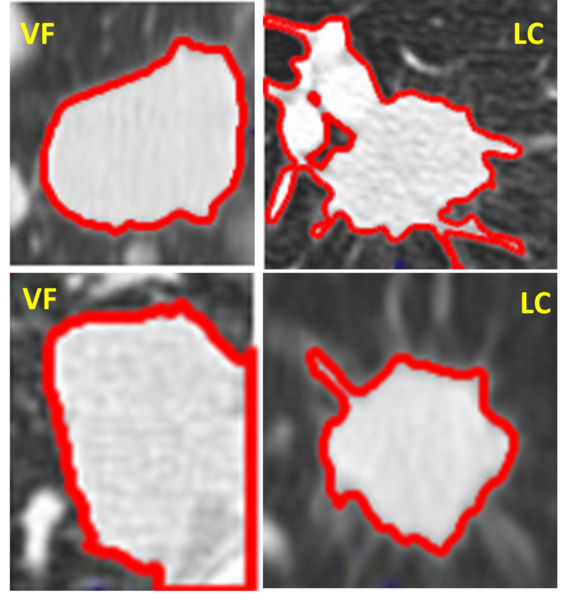

Read More...The use of computer vision to differentiate valley fever from lung cancer via CT scans of nodules

Pulmonary diseases like lung cancer and valley fever pose serious health challenges, making accurate and rapid diagnostics essential. This study developed a MATLAB-based software tool that uses computer vision techniques to differentiate between these diseases by analyzing features of lung nodules in CT scans, achieving higher precision than traditional methods.